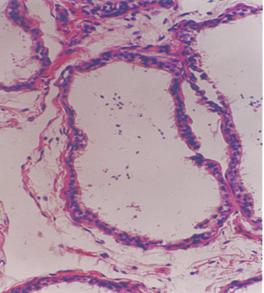

精曲小管橫切面隱睪與不孕症。隱睪由於組織病理學的改變,沒有正常的生精功能,隱睪的位置越高,在陰囊以上的位置時間越長,睪丸曲細精管的損害越大。Mengel經用普通顯微鏡和電子顯微鏡觀察,隱睪病人睪丸在2歲以前就有曲細精管和間質細胞的病理學改變及明顯的生精損害。Hecker檢查正常成人及單側隱睪病人經睪丸固定術以後的精子濃度,前者明顯高於後者,表明單側隱睪病人有雙側隱睪損害。雙側隱睪病人未經治療,不孕症可達100%,如早期治療生育力可達40%。而單側隱睪早期治療後生育力可達60%。

曲精細管隱睪與睪丸扭轉,由於隱睪病人睪丸與系帶之間常有發育異常,故易發生睪丸扭轉。進入青春期後由於睪丸體積增大發生機會更多。Rigter報告64%的成人隱睪扭轉是由於睪丸發生惡性變,以至睪丸重量及睪丸重力軸改變而發生。